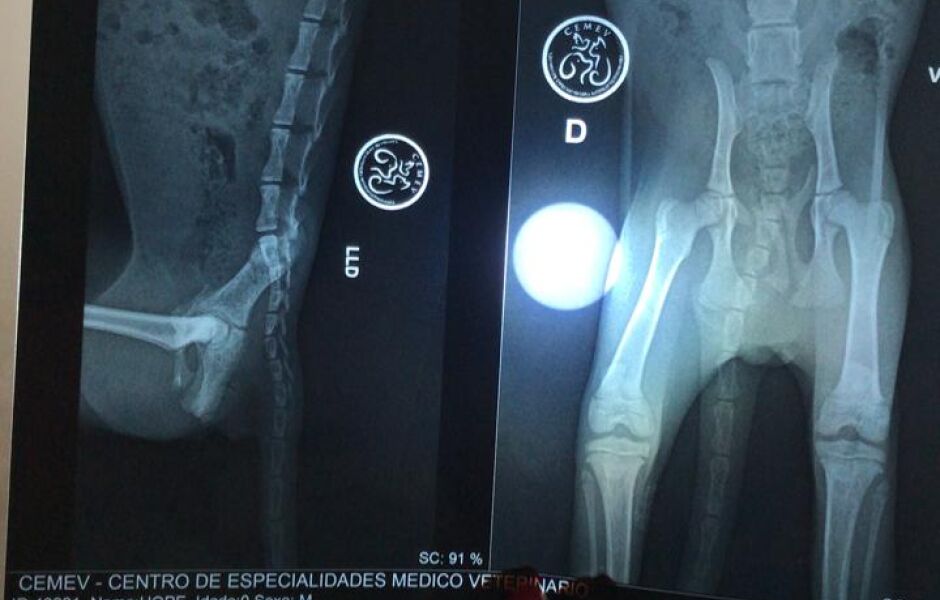

Para ajudar uma gatinha de três meses que encontrou machucada, a jovem Viviane Riquelmes, de 23 anos, esta fazendo uma rifa para pagar o tratamento. De acordo com o médico veterinário que atendeu o caso, Hope, como foi apelidada a gata, esta com fratura em quatro partes da pelve.

Ao perceber que algo estava errado, ela começou a pedir ajuda para custear a primeira consulta no veterinário. “Eu tive muitos amigos que me ajudaram muito, graças ao pessoal consegui levar a Hope rápido ao veterinário”, explica ela. “Lá descobrimos quatro fraturas na pelve, possivelmente causadas por agressões. Ainda bem que não foi preciso fazer cirurgia, apenas com os remédios e cuidados em casa ela vai se recuperar bem”, finaliza.